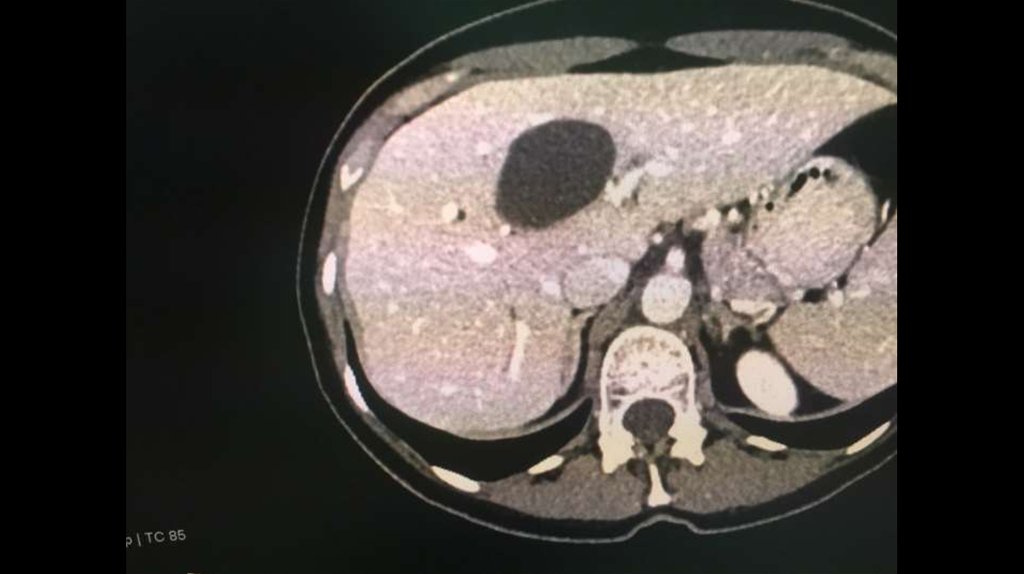

По направлению из ЦГБ в ККБ №1 поступил пациент М., 48 лет, с диагнозом «Эхинококкоз

печени»

Пациенту в плановом порядке выполнено КТ ОБП. По результатам исследования выявлена

эхинококковая киста IV-V сегментов.